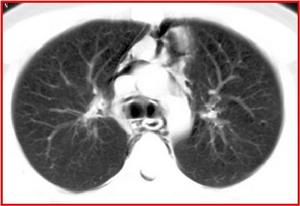

2.CT表現可顯示環繞縱隔內的氣體密度線條狀影,縱隔胸膜向肺野方向推移。縱隔內空氣常向上沿頸筋膜間隙向胸部皮下擴散,產生皮下氣體密度影。